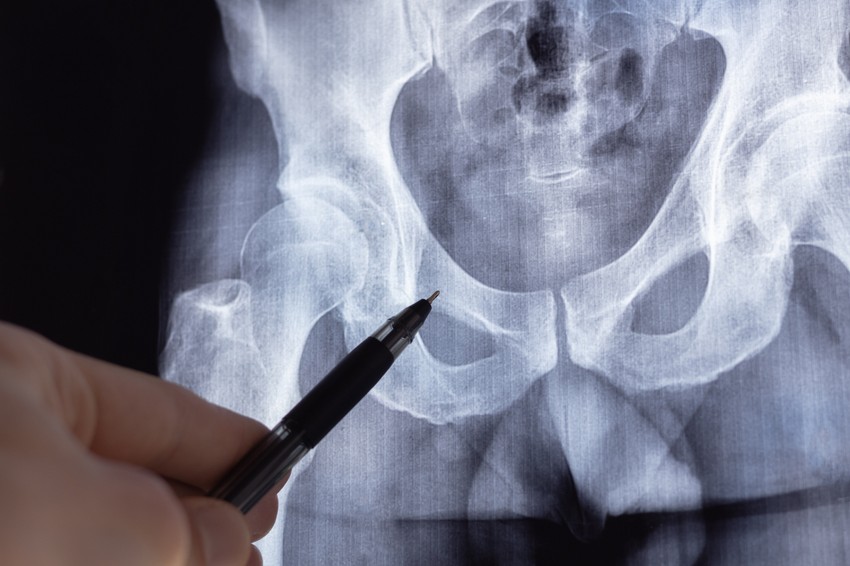

A tünetek és a fizikai vizsgálat alapján sejteni lehet a diagnózist. A diagnózis megerősítése egyrészt röntgenfelvételekkel történik, melyeken jól láthatók a betegségre jellemző kóros csontelváltozások, másrészt laborvizsgálattal, mely a csontsejtek képződésében szerepet játszó enzim, az alkalikus foszfatáz vérszintjét mérik.

A Paget-kór egy olyan állapot, amely két fő formában létezik: az egyik a csontanyagcsere rendellenessége (osteitis deformans), ami a csontok törékennyé és deformálódottá tételét okozza, leggyakrabban a medencében, koponyában, gerincben és lábakban; a másik a bőr, emlő vagy nemi szervek Paget-kórja, amely a hámsejtek kóros elburjánzása, gyakran egy alapuló daganat jele, és nem gyógyuló sebeket, kiütéseket, viszketést és váladékozást okoz. A diagnózis fizikális vizsgálattal, biopsziával (szövettani mintavétel), képalkotó vizsgálatokkal (röntgen, CT, MRI) és vérvizsgálattal (alkalikus foszfatáz szint) történik, a kezelés pedig a tünetek és a forma függvénye.